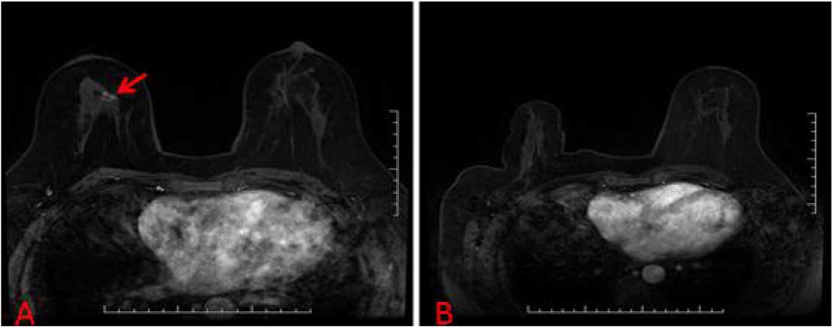

下面列举几个病例的MRI图像:

病例2:57岁女性,T1加权脂肪抑制增强MRI显示左乳可疑病变,BI-RADS分级为4C级 (A);病灶(红色箭头)在MRI引导下行导丝定位(蓝色箭头),经手术活检发现为浸润性导管癌 (B)。